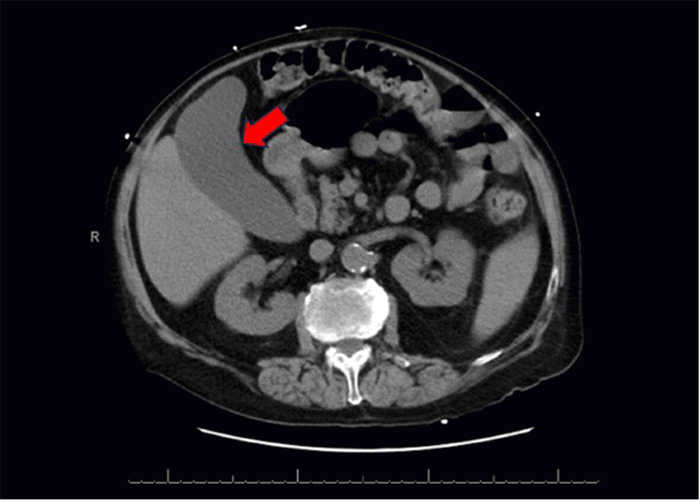

Figure 4. CT Demonstrating Anterior Diaphragmatic (Morgagni) Hernia. Published with Permission

Axial reformatted CT scan of the lower chest and upper abdomen. Note right-sided anterior diaphragmatic defect through which omentum and loops of small bowel (red arrow indicating herniated contents) are seen traversing the right hemidiaphragm and extending into the region of the epicardial fat pad, consistent with a Morgagni hernia

On physical exam, the patient was afebrile and hemodynamically stable. His abdomen exhibited mild RUQ tenderness on palpation; however, Murphy’s sign was absent, and there was no rebound tenderness or guarding. Initial laboratory evaluation revealed a mild anemia, while aminotransferase, alkaline phosphatase, and lipase levels were within normal limits. A computed tomography angiogram (CTA) of the abdomen and pelvis re-demonstrated significant gallbladder distension and showed non-enhancing, hyperdense material consistent with a large blood clot occupying approximately 75% of the gallbladder lumen, diagnostic of hemorrhagic cholecystitis (Figure 3). Additionally, a right-sided anterior diaphragmatic hernia, consistent with a Morgagni hernia, was incidentally found, containing omentum and loops of small bowel without evidence of obstruction (Figures 4 and 5). By the second day of admission, repeat laboratory tests showed a new elevation in liver enzymes (AST 130 IU/L, ALT 101 IU/L, alkaline phosphatase 250 IU/L) and a decline in hemoglobin from 10.7 to 9.0 g/dL. Following a multidisciplinary conference involving hematology, neurology, and perioperative care services, a decision was made to proceed with urgent surgical intervention.